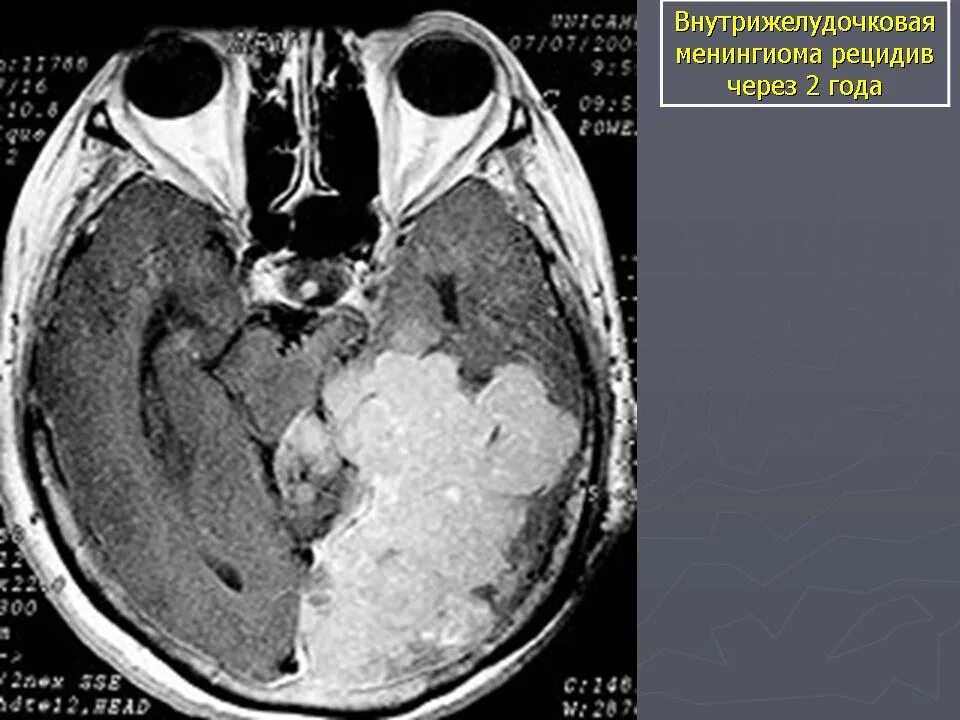

Менингиомы головного мозга мкб